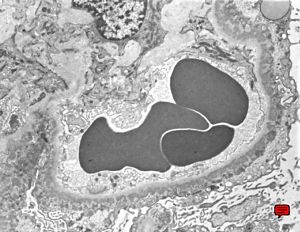

M,29y. | type II membranoproliferative glomerulonephritis (dense deposit disease)